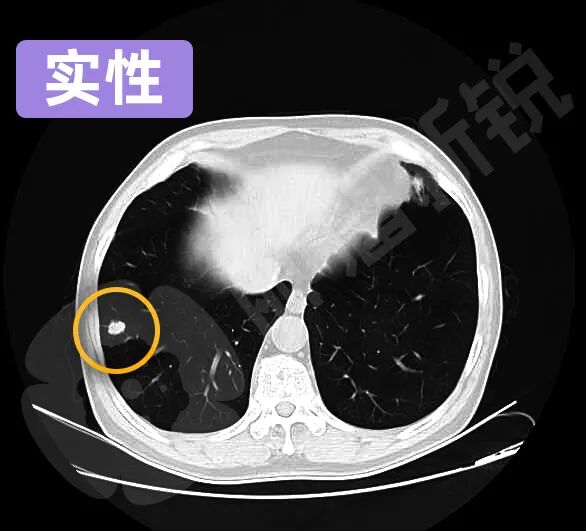

根据磨玻璃结节所包含的实性成分的不同,又可以分为纯GGO、混杂GGO、半实性GGO等不同亚型。

实性GGO在图像上可以明确分辨,边界清晰。